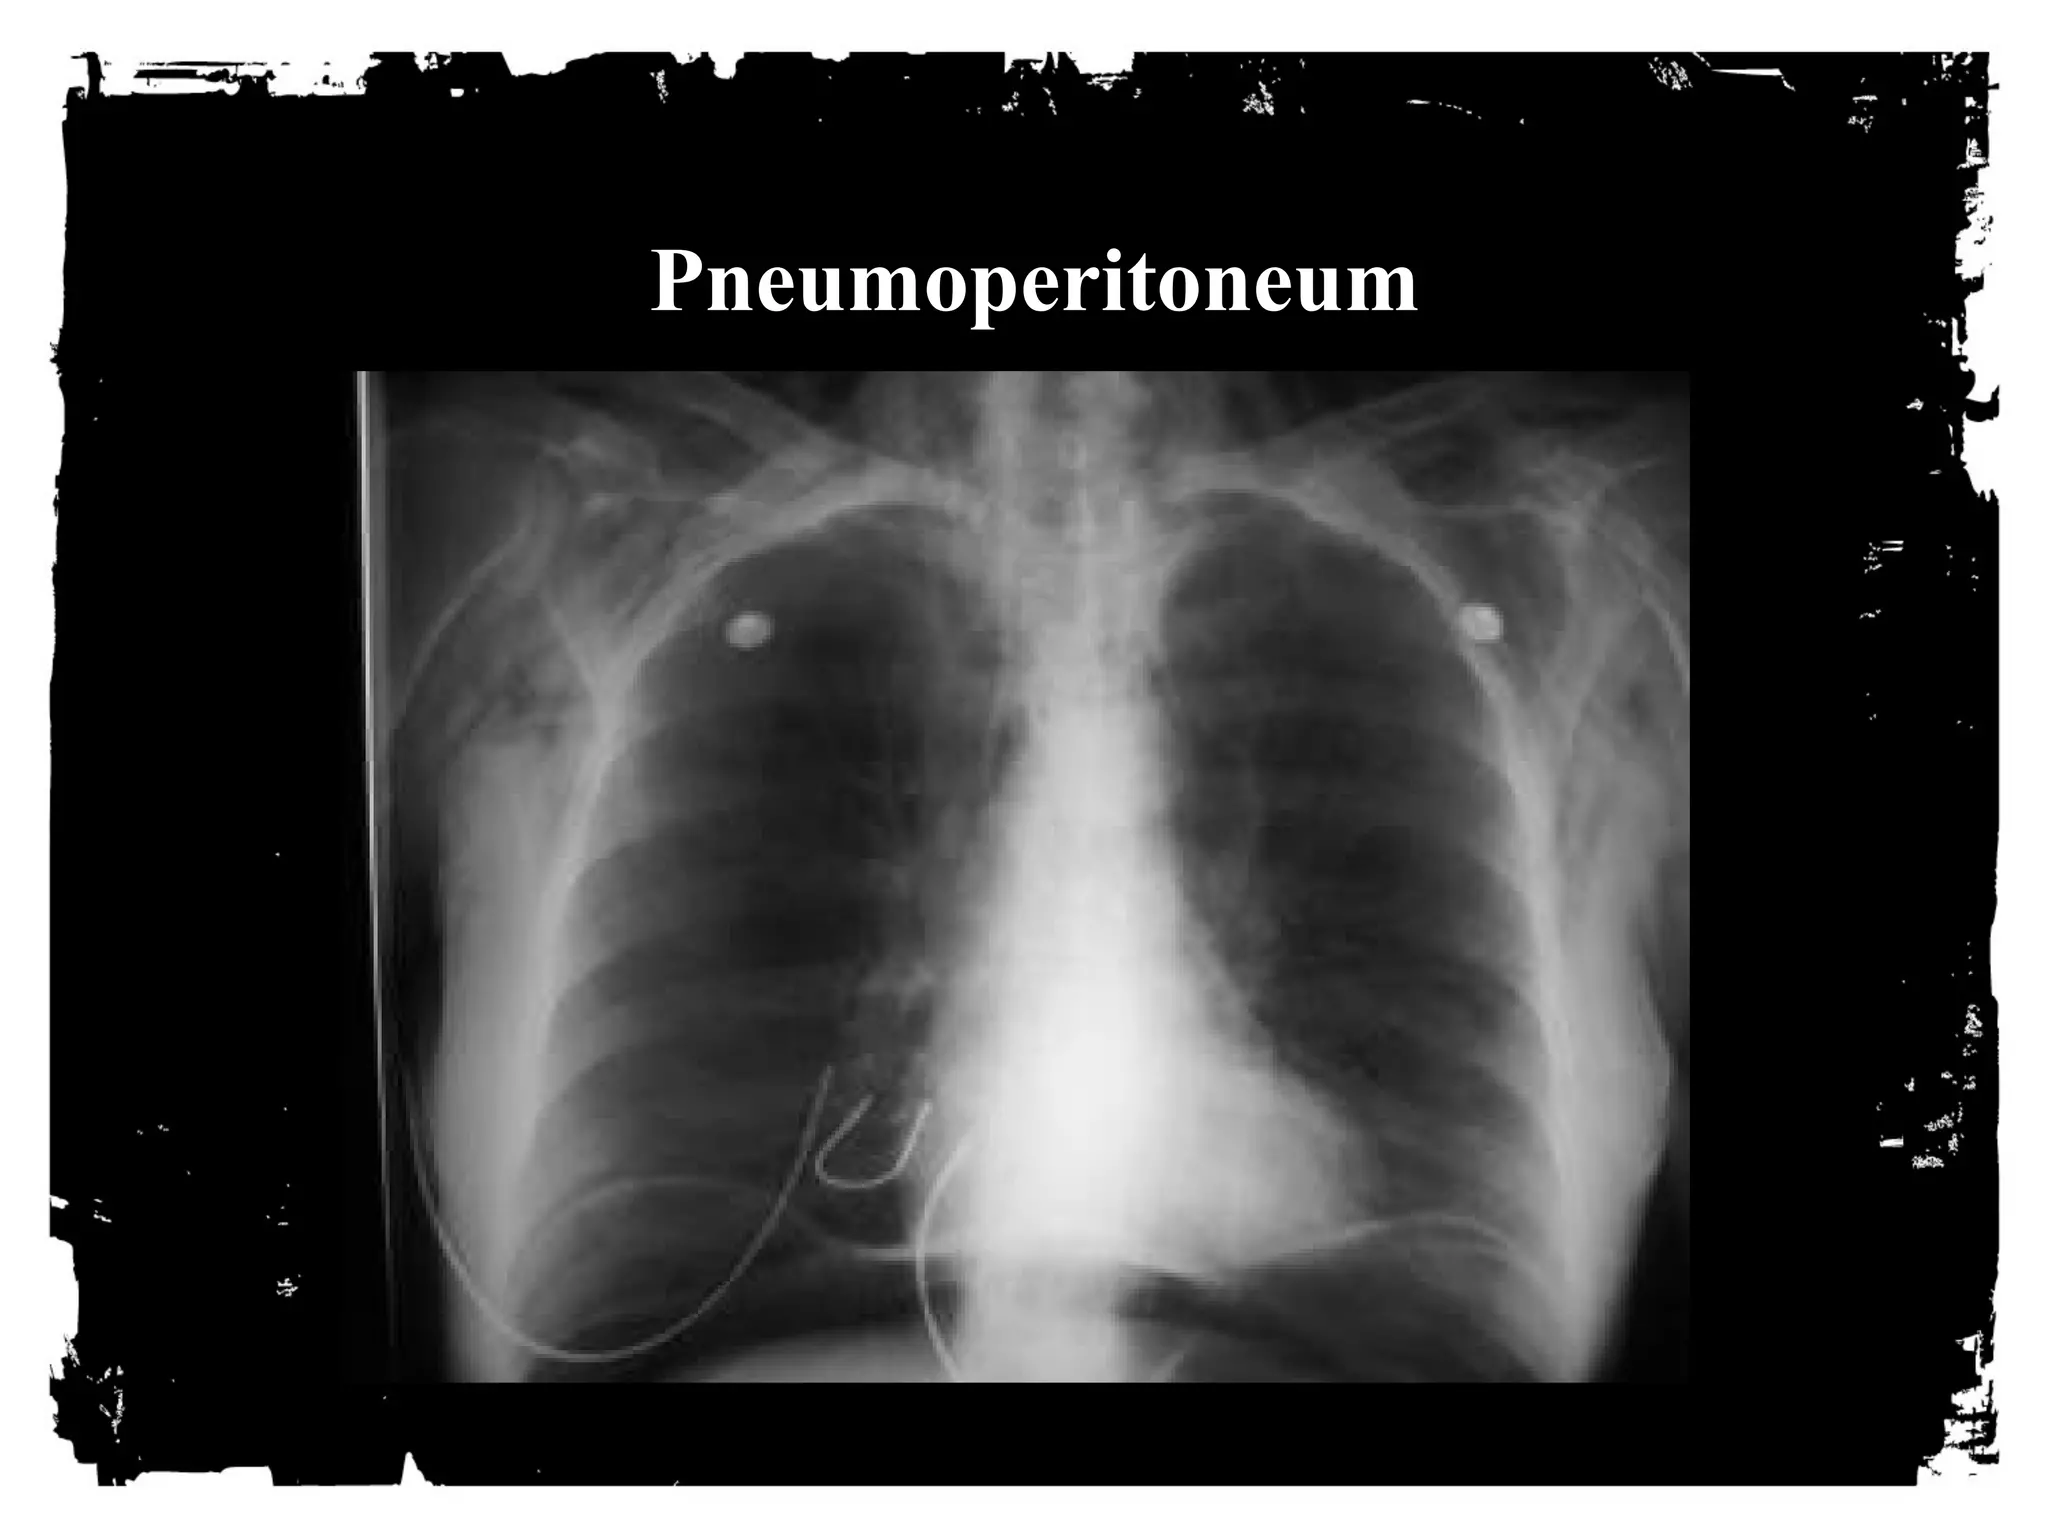

Pneumoperitoneum

Systemic venous air embolism